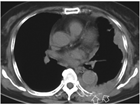

1. 胸腔鏡で腫瘍が確認されない最も早期の胸膜中皮腫である”mesothelioma in situ(前浸潤性中皮腫)” の存在は以前から知られていたが、『WHO分類 第5版』に初めて明記された。

1. 早期の胸膜中皮腫と反応性中皮細胞増生(反応性中皮過形成)の病理像は類似し、良悪の鑑別は慎重に行う必要がある。BAP1免疫染色、CDKN2A遺伝子の中皮腫でのホモ接合性欠失の検出が鑑別に役立つ。